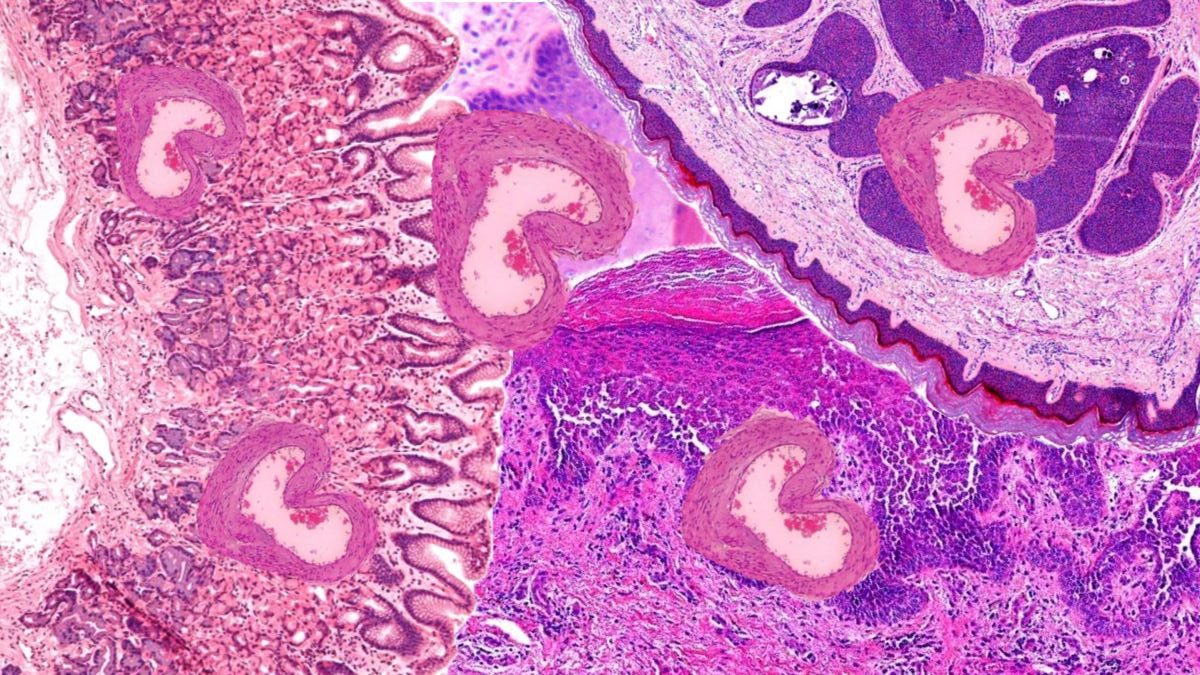

Dirofilariasis

Clinical backgroundEtiology: Human dirofilariasis is caused by Dirofilaria repens (subcutaneous/ocular) and Dirofilaria immitis (pulmonary). Humans are accidental, dead-end hosts. Transmission: Mosquito-borne from infected dogs or wild carnivores. Presentation: 1. D. repens: Subcutaneous or ocular nodules, often painless. 2. D. immitis: Pulmonary “coin lesions,” usually asymptomatic.Lab findings: Peripheral eosinophilia is inconsistent. Serology is unreliable. Imaging may…